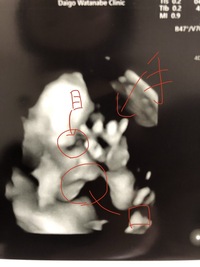

①エコー検査 妊娠11~14週頃に行うエコー検査で、赤ちゃんのうなじのあたりに、通常の赤ちゃんよりも厚い皮膚の浮き上がりが見られる場合、ダウン症が疑われます。 しかしエコー検査だけでは確定診断には至りません。 ②母体血清マーカーテストエコーで男の子なら、シンボルマーク 女の子なら、唇のような木の歯のような形で、分かると 思いますが、実際は、産まれて来るまでのお楽しみですね(^^) 一般的には、6ケ月か7ケ月だと思いますが、恥ずかし がり屋さん(大事なところを隠している)は、9ケ月と 言う赤ちゃんもいますよ。 · 妊娠9ヶ月、3dエコーで赤ちゃんの口唇口蓋裂が判明 妊娠32週目のときに口唇口蓋裂の疑いが 妊娠検査薬で妊娠がわかってから、家の近くにある個人産院で妊婦健診を受けていました。

18/8/16 · 女性ってすごい!4Dエコーで命の神秘のすごさに驚きました! 16/8/18 この記事をシェアする 4Dエコーを体験!はるにゃんさんのマタニティエッセイ。 4Dを見てからわが子に会うのが楽しみで仕方ありません。 コモドライフの皆様こんにちは!現在日本でのダウン症の方は8万人、発症率は700人に1人といわれています。 高齢出産だとダウン症の確率が高くなる、遺伝するなどといった情報もよく耳にするのではないでしょうか。 妊娠期間中どのくらいの時点で判明するのか、ど赤ちゃんの指は、気を付けてよく見ると、早ければ4 指に限らず、四肢、四肢の骨、脊椎、唇 ① 向きの関係や超音波の映り方の関係ではっきり見えない(肥満で腹壁が厚い